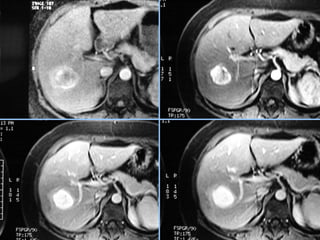

Hemangioma

 Fase art.      Fase portal    Fase tardia

 S/C              Fase art.

 Fase portal      Fase tardia

 S/C      Fase art.    Fase tardia